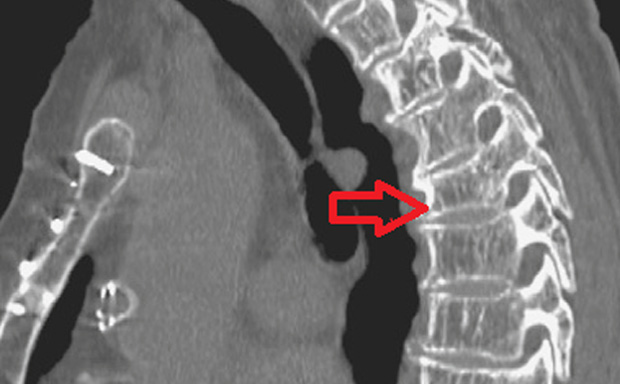

Количественная компьютерная томография

Компьютерная томография (КТ) позволяет получить трехмерное изображение скелета. Этот метод позволяет:

- определить минеральную плотность каждого слоя кости;

- исследовать плотность костной ткани и анатомическое расположение позвоночника;

- с высокой точностью оценить содержание минералов в костной ткани с помощью двухэнергетической КТ;

- выявить степень деформации тел позвонков.

По сравнению с двухэнергетической рентгеновской абсорбциометрией и ультразвуковой количественной денситометрией, результаты КТ обладают более высокой валидностью.

Однако у метода есть и недостатки. На результаты исследования влияет содержание жировой ткани в костном мозге, которое увеличивается с возрастом пациента. Длительные исследования с использованием КТ могут привести к значительной дозе облучения. Кроме того, такие исследования дорогостоящие и не всегда доступны.

Из-за этих недостатков компьютерная томография при диагностике остеопороза все чаще заменяется другими, более доступными и надежными методами денситометрии.